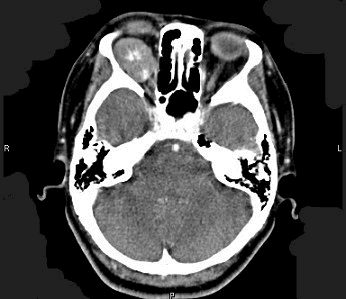

患者,女性,60岁,高血压病史20年。2小时前突发左眼视力丧失,自诉似“电灯开关关闭”。眼底检查。

(如图)最可能的诊断是()

-

最有特征的体征是()

该病的急诊处理原则是()